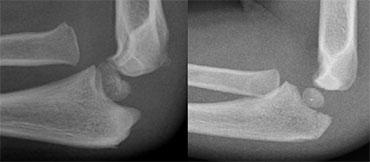

LEFT: an obvious radial dislocation. No fracture of the ulna (Monteggia) was foundRIGHT: a subtle radial head dislocation. Associated olecranonfracture is seen on carefull inspection

Dislocations of the Radial head

Trật khớp đầu xương quay có thể rất rõ ràng.

Tuy nhiên, không hiếm trường hợp những trật khớp này khó nhận thấy và dễ bị bỏ sót.

Trong mọi trường hợp, cần tìm kiếm các tổn thương kèm theo.

Trong mô tả ban đầu của Monteggia, có sự trật khớp đầu xương quay kết hợp với gãy thân xương trụ đoạn gần.

Tuy nhiên, gãy xương ở bất kỳ vị trí nào dọc theo xương trụ cũng đã được ghi nhận.

Đặc biệt, gãy xương mỏm khuỷu kèm theo rất phổ biến (hình).

Olecranon fractures

Gãy mỏm khuỷu ở trẻ em ít phổ biến hơn so với người lớn. Như đã đề cập ở trên, chúng thường liên quan đến gãy cổ xương quay và trật khớp xương quay.

Gãy mỏm khuỷu (3)

Bên trái là một số ví dụ về gãy mỏm khuỷu.

Lưu ý một số trường hợp gãy xương này rất khó nhận thấy.